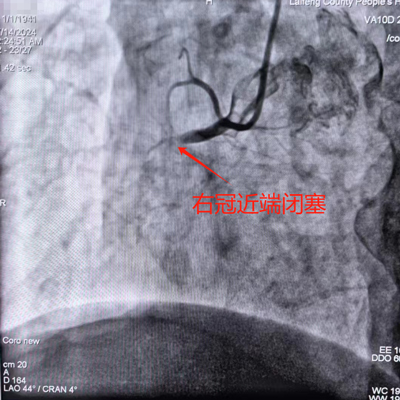

02:30 完成冠脉造影。

02:35 植入临时起搏器。